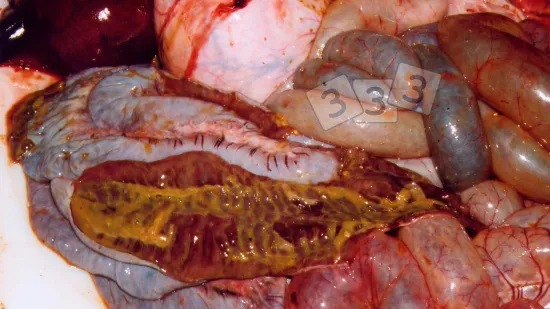

Semaine du 01-Avr-2024

À l'abattoir, la présence de zones rouges de consolidation cranio-ventrale (hépatisation) a été détectée dans ce poumon, suggérant une pneumonie enzootique. Quel est l'agent principal associé à cette condition ?